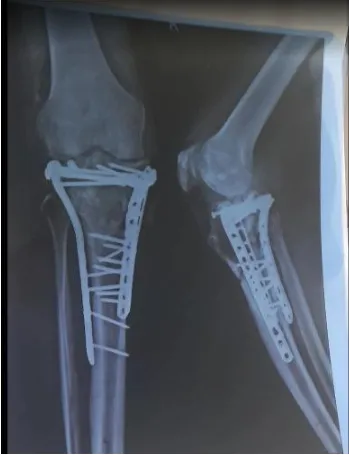

Patient Name: Mr. B.K. ( initials written due to privacy reasons)

Age / Gender: 48 / Male

Health Concern / Symptoms Reported:

Mr B.K. suffered from a major knee injury, leading to significant pain and mobility issues.

Diagnosis:

The patient was diagnosed with a severe knee injury that required surgical intervention.

Treatment Given:

The injury was managed with expert surgical care. The treatment included stabilising and repairing the knee using advanced orthopedic techniques.

Outcome / Result:

Post-surgery, the patient showed substantial improvement, with reduced pain and regained mobility. He is currently on the path to full recovery.

Photos Before/After:

X-ray images attached showing the surgical results. The patient expressed complete satisfaction with the treatment, emphasising the effectiveness of the surgical approach and the quality of care.

The patient’s recovery was successful due to the appropriate surgical intervention, highlighting the effectiveness of modern orthopedic procedures.